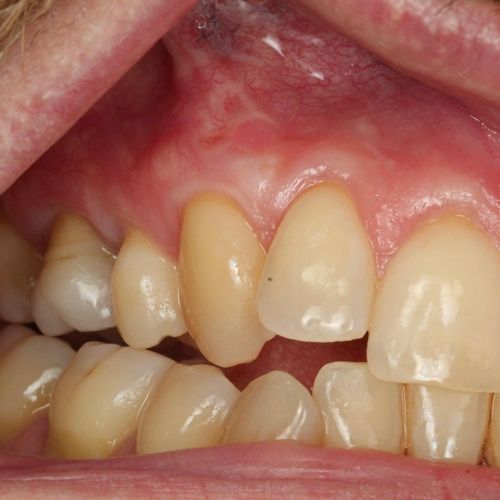

Before and after Periodontal Therapy

![]() | ![]() |

| Untreated severe gum disease | Gum disease treated and stabilised by Dr Halai |